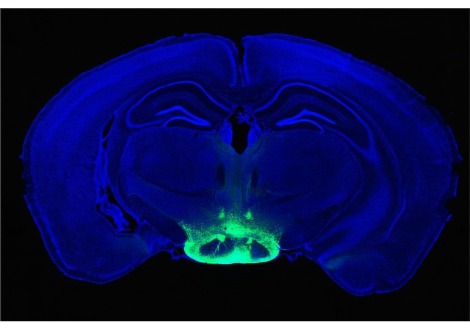

درس براون منذ فترة طويلة كيفية تأثر إيقاعات الدماغ عند البشر تحت التخدير العام عن طريق إجراء وتحليل قياسات الإيقاعات باستخدام أقطاب تخطيط كهربية الدماغ لفروة الرأس ، وإلى حد محدود ، الأقطاب القشرية في مرضى الصرع. نظرًا لأن الدراسة الجديدة أجريت على نماذج حيوانية لتلك الديناميكيات ، فقد تمكن الفريق من زرع أقطاب كهربائية يمكنها قياس نشاط أو "ارتفاع" العديد من الخلايا العصبية الفردية والإيقاعات في القشرة والمهاد. قال براون إن النتائج تعمق بشكل كبير وتوسع نطاق النتائج التي توصل إليها في الناس.

على سبيل المثال ، نفس الخلايا العصبية التي قاموا بقياسها بالثرثرة مع ارتفاعات الجهد 7-10 مرات في الثانية أثناء اليقظة ، يتم إطلاقها بشكل روتيني مرة واحدة فقط في الثانية أو أقل أثناء فقدان الوعي الناجم عن البروبوفول ، وهو تباطؤ ملحوظ يسمى "حالة السقوط". إجمالاً ، أجرى العلماء قياسات متزامنة مفصلة للإيقاعات والارتفاعات في خمس مناطق: اثنتان في مقدمة القشرة ، واثنتان في الخلف ، والمهاد.